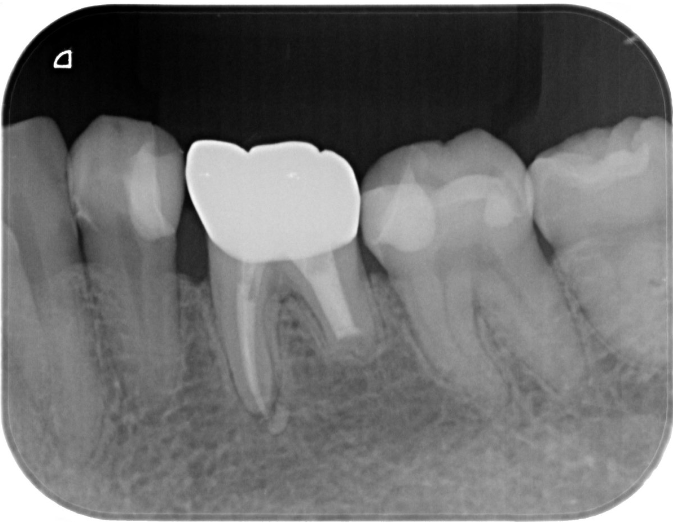

症例3

| 項目 | 詳細 |

|---|---|

| 患者様データ | 40代 男性 |

| 来院時の主訴 | 「前歯を歯磨きすると痛いし、出血する。」 |

| 医院の診断 | 右上中切歯根尖性歯周炎、歯周病 |

| 通院期間 |

6か月 |

| 来院回数 | 10回 |

| 治療費 | 総額:歯周病治療に関しては保険適用診療。その他:370,000円(税抜) 【内訳】 歯周病治療(歯周病検査・歯磨きや生活習慣指導・歯石取りクリーニング) その他、精密根管治療 70,000円、ファイバーポストコア 20,000円、セラミック治療 140,000円×2 |

| リスクと副作用 | メインテナンスが必要、正しい歯磨き習慣が必要不可欠 |

| ここがこだわりのポイント!☝ | こちらは中等度の歯周病と虫歯を併発されていた患者様です。日々の歯磨き習慣を見直していただき、正しいブラッシング法を身につけたことで健康な歯肉を取り戻しました!短期間での治療を希望されていたので審美的な歯肉ラインの獲得はできませんでしたが、健康的な歯肉を獲得できました。 |